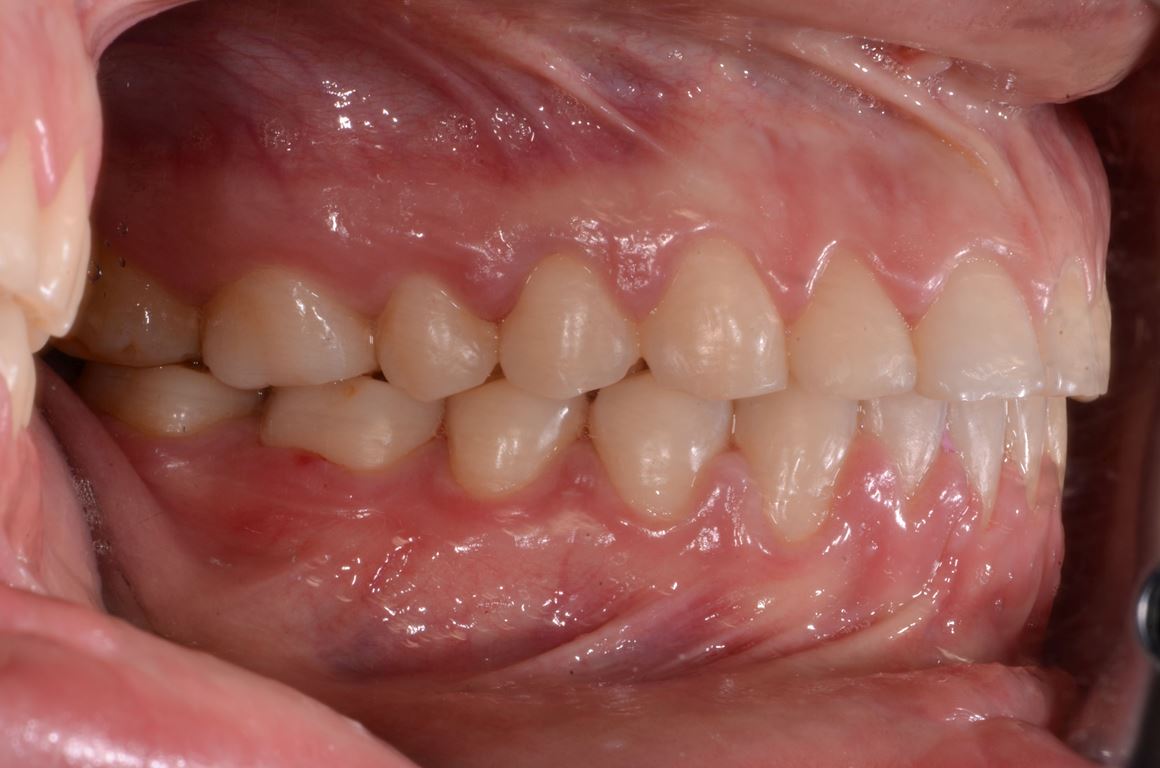

Bezpośrednio po usunięciu zębów rozpoczęto leczenie ortodontyczne, które trwało 15 miesięcy i pozwoliło na uzyskanie zaplanowanych wcześniej pozycji zębów (ryc. 22-24).

Następnie, po okresie stabilizacji i wstępnej korekcie okluzji, na podstawie analizy nowego kompletu zdjęć i modeli, wykonano woskowanie diagnostyczne oraz mock-up górnego łuku zębowego mający na celu potwierdzenie ostatecznego kształtu zębów i zakresu niezbędnego przygotowania chirurgicznego (ryc. 25-27).